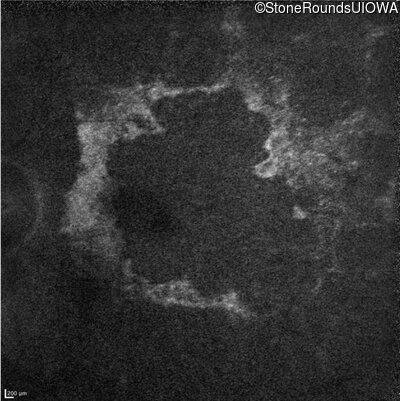

Age at visit: 38 years

This 38 year old woman had normal vision until age 22 when she noticed poor night vision when working as a camp counselor after college. Her hearing loss was first noticed at age 3 and was correctable with hearing aids.

Age at visit: 38 years (Visit 2)